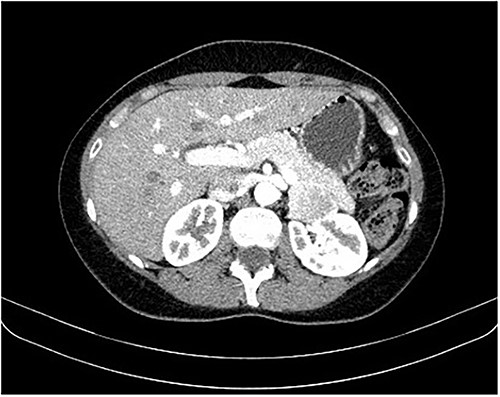

During a screening imaging examination of her liver disease, a lesion suspected of malignancy was detected. The ultrasound disclosed a hypoechoic nodule, vaguely heterogeneous, located in segment VII, subcapsular, and with ~22 mm in diameter (Fig. 1). Liver blood tests and serum alpha-fetoprotein level were normal. For better characterization, a CT scan was performed. The CT showed, in addition to signs of chronic liver disease, the presence of a solid subcapsular nodule of segment VII, measuring 23 mm, with hypervascular behavior in the arterial phase (Fig. 2) and washout in late venous phase (Fig. 3).

CT scan showing, in addition to signs of chronic liver disease, the presence of a solid subcapsular nodule of segment VII, measuring 23 mm, with hypervascular behavior in the arterial phase.

CT scan showing the same mass as shown in Fig. 2 but with washout in the portal venous phase.

Based on the imaging characteristics and the patient's history, hepatocellular carcinoma was assumed and its surgical excision was proposed. The patient underwent intraoperative ultrasound and laparoscopic resection of the liver lesion, with macroscopic margins of ~1 cm. The procedure and the postoperative period were uneventful.